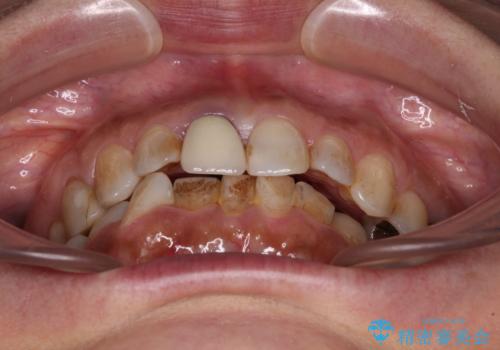

痛みがなくなり歯列が整ったことで、残っている銀歯も気になり始めているようです。

マウスピース生活に疲れてしまったとのことで、暫くお休みをしてから銀歯の治療を再開していく予定です。